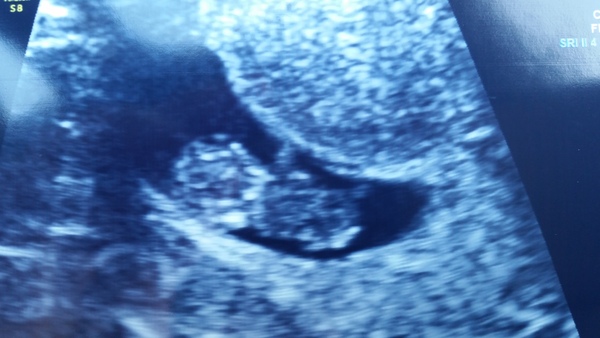

lilydaisyrose · 11/05/2016 21:02

Have to share my scan at 9w+3d today - with a lovely strong heartbeat. Over the moon. I am hoping my chances are very good now.